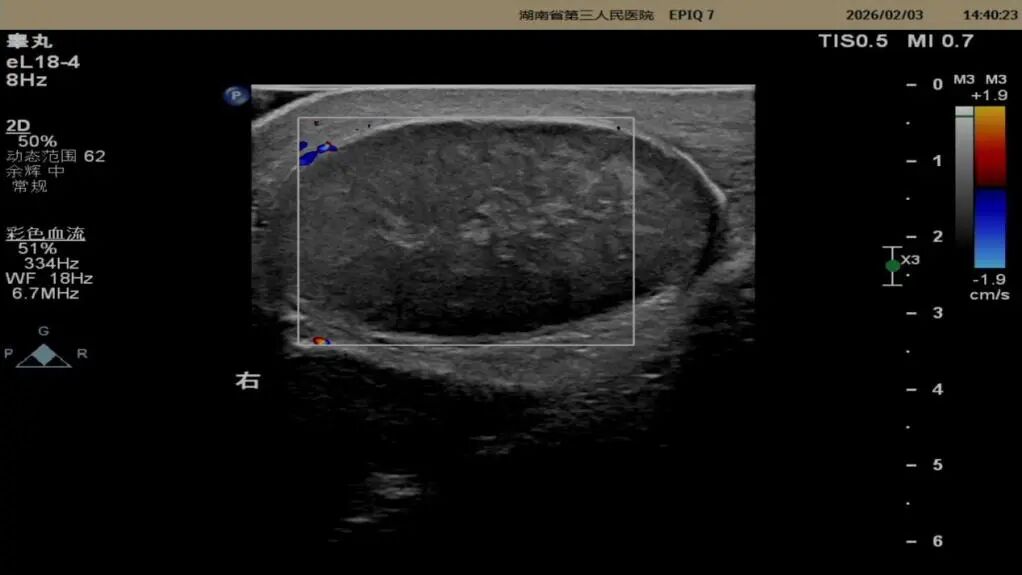

超声影像图像如下:

右侧坏死睾丸血流信号图像。

二维超声:看结构,辨异常

▷坏死睾丸:超声下可见睾丸实质回声减低、不均匀,失去正常的均匀光点,提示睾丸组织已受损;

CDFI(彩色多普勒血流成像):看血流,定生死

这是诊断睾丸坏死的核心依据:坏死的睾丸因血液供应完全中断,超声下内部无明显血流信号;而正常睾丸或未完全坏死的睾丸,会显示丰富的血流信号。需要注意的是,扭转的精索包块内可能仍有少量血流,需结合二维超声综合判断,避免误判。